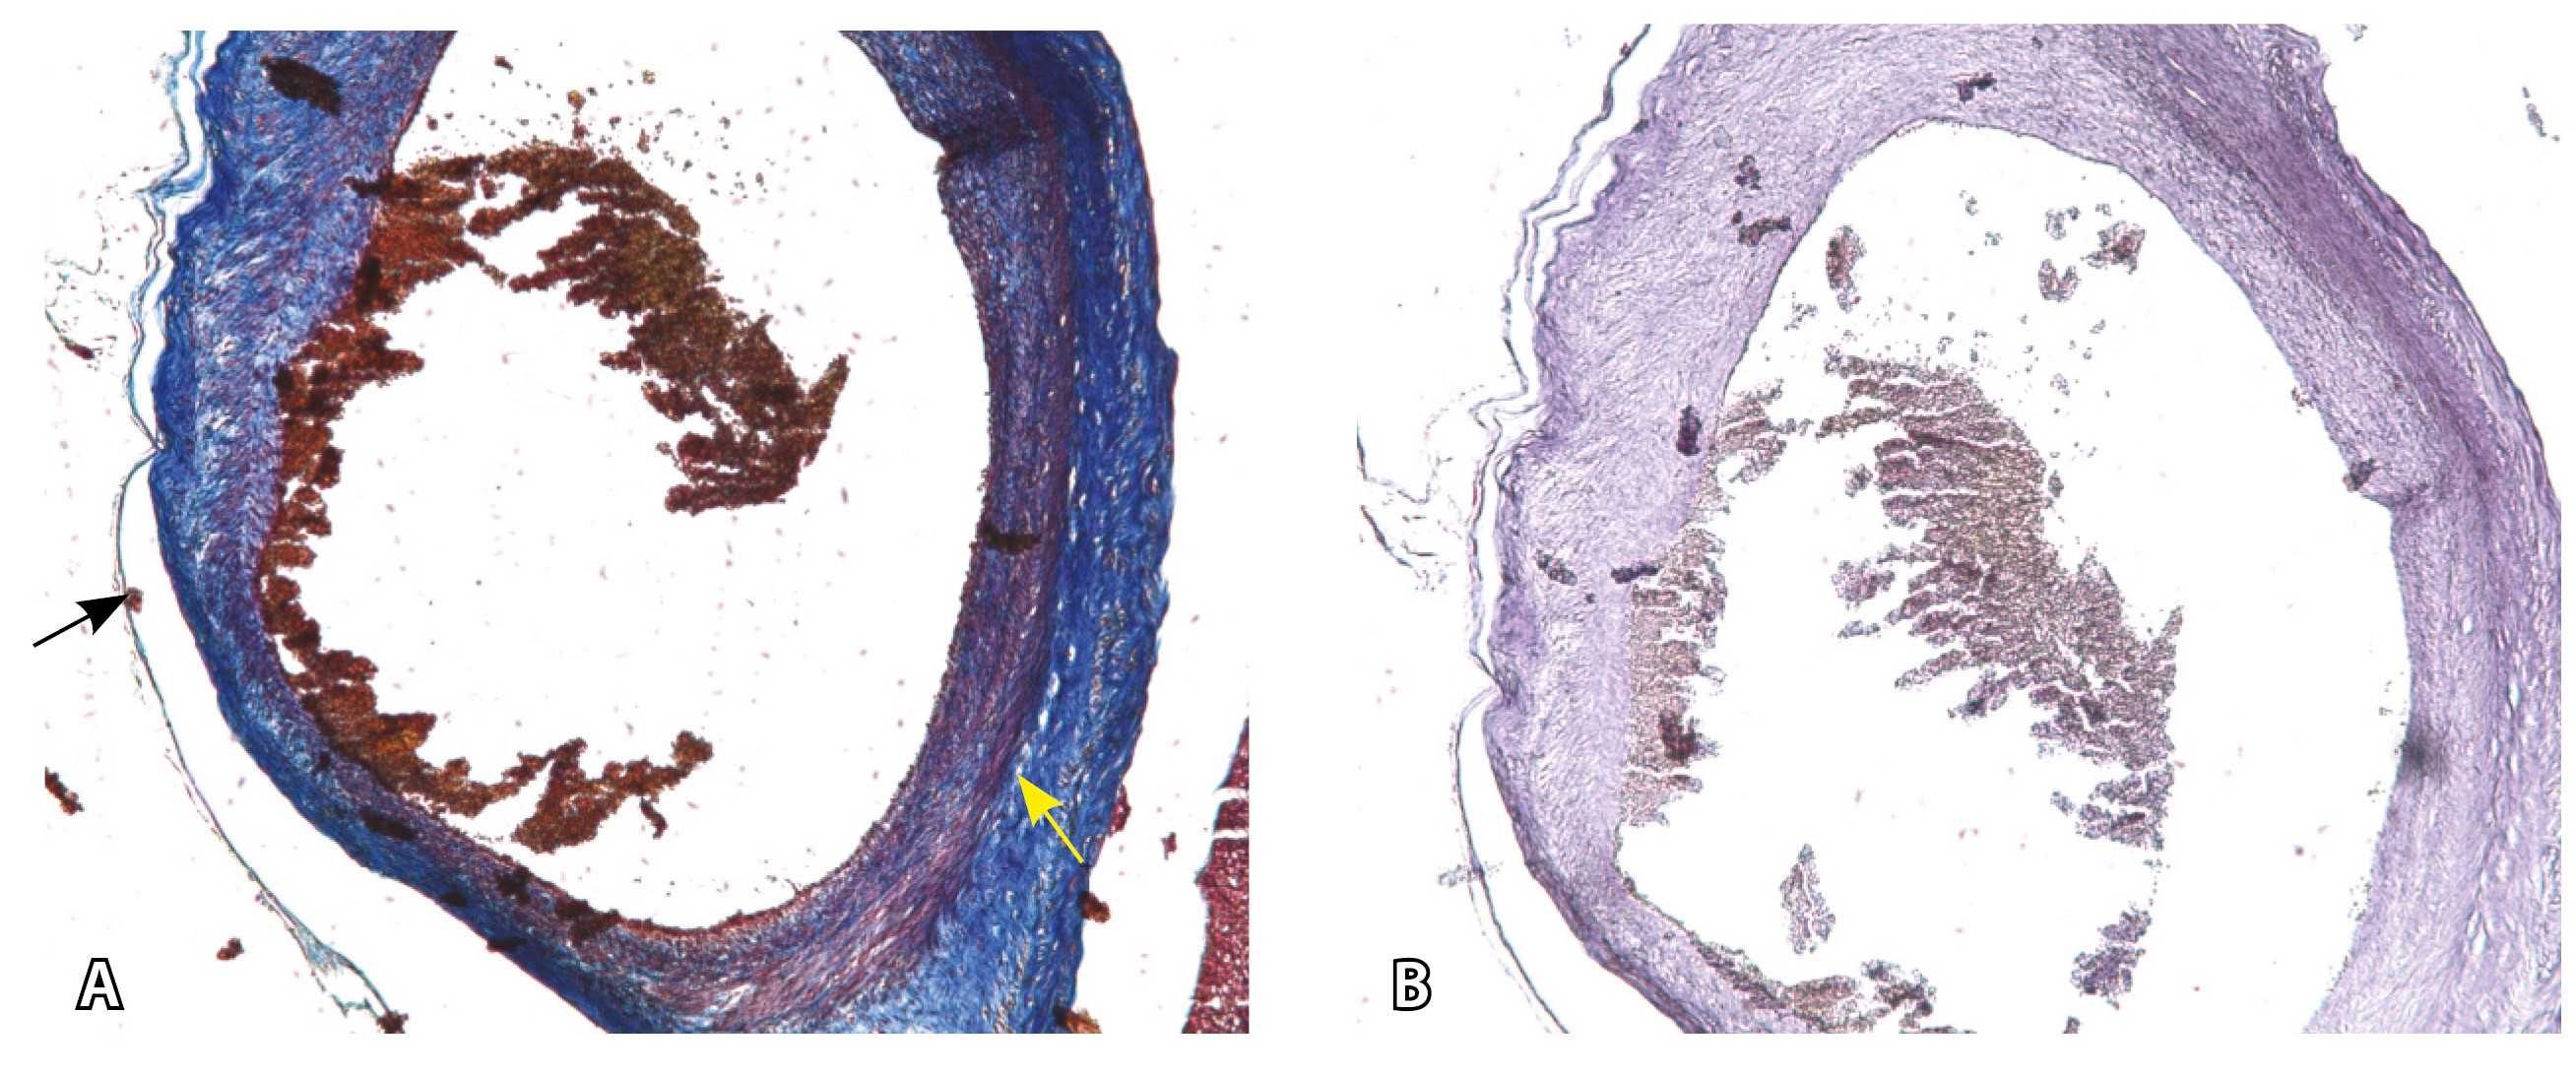

Рис. 13. Самые крупные сосуды в пределах серозной оболочки стенки матки: А, Б – серийные срезы артерии; × 50. При окраске по Маллори (А) видна тонкая полоска мезотелия (черная стрелка), слабо дифференцированная мышечная стенка артерии, вокруг нее – плотная коллагеновая оболочка (желтая стрелка), в просвете определяются тромботические массы. При окраске по Вейгерту (Б) наблюдается полная потеря внутренней и внешней эластических мембран

Эластический каркас представлен сетью тонких волокон, без концентрации на внутреннюю и внешнюю мембраны. Однако маркер СD34 констатирует сохранение эндотелия, что свидетельствует о том, что по артериям циркулирует кровь, не сворачиваясь (рис. 13).

На микропрепаратах васкуляризация серозной оболочки представлена множеством крупных сосудов, идущих в разных направлениях и анастомозирующих друг с другом. Возможно, имеются артериовенозные соустья. На серийных срезах также видно, что в стенках артерий трудно различимы два слоя миоцитов (продольный и поперечный). Со стороны адвентиции они окружены толстым «футляром» из грубоволокнистой голубой ткани (при окраске по Маллори). Она проникает в стенку артерий, замещая мышечный слой (рис. 12).

Главным отличием крупных сосудов в составе серозной оболочки является то, что морфологически они находятся в пределах стенки матки. Об этом свидетельствует наличие в операционном материале тонкого поверхностного слоя мезотелия, отделяющего матку от брюшной полости (рис. 11). Его невозможно визуализировать методом МРТ из-за особенностей метода и толщины получаемых срезов.